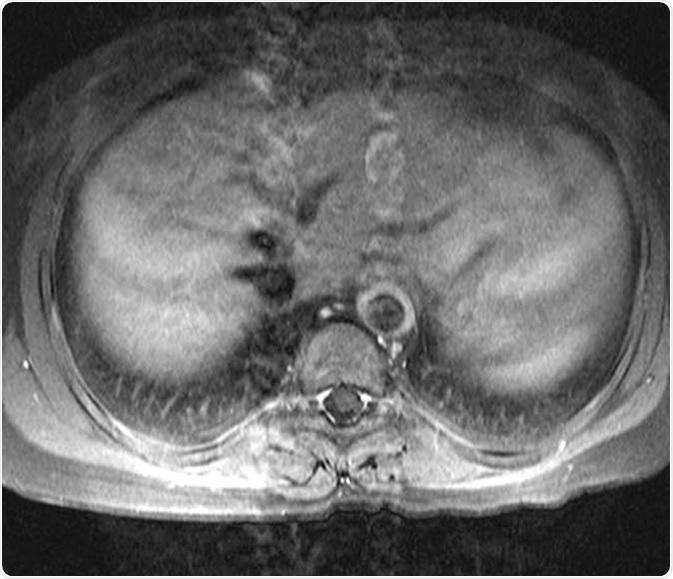

15 year-old female patient with known Takayasu arteritis presented for MRI to investigate back pain. The axial T1-weighted post-gadolinium MRI above shows thickened, enhancing aortic wall, consistent with large vessel vasculitis. Dr Laughlin Dawes, http://www.radpod.org/2007/04/15/takayasu-arteritis/

MRI produces high resolution images that show features of vascular inflammation. The thickening of vessel walls takes place very early in the inflammatory stage of the disease, which can be detected by MRI. This shows how important MRI is in the detection of early disease stages, when damage is more likely to be reversible.